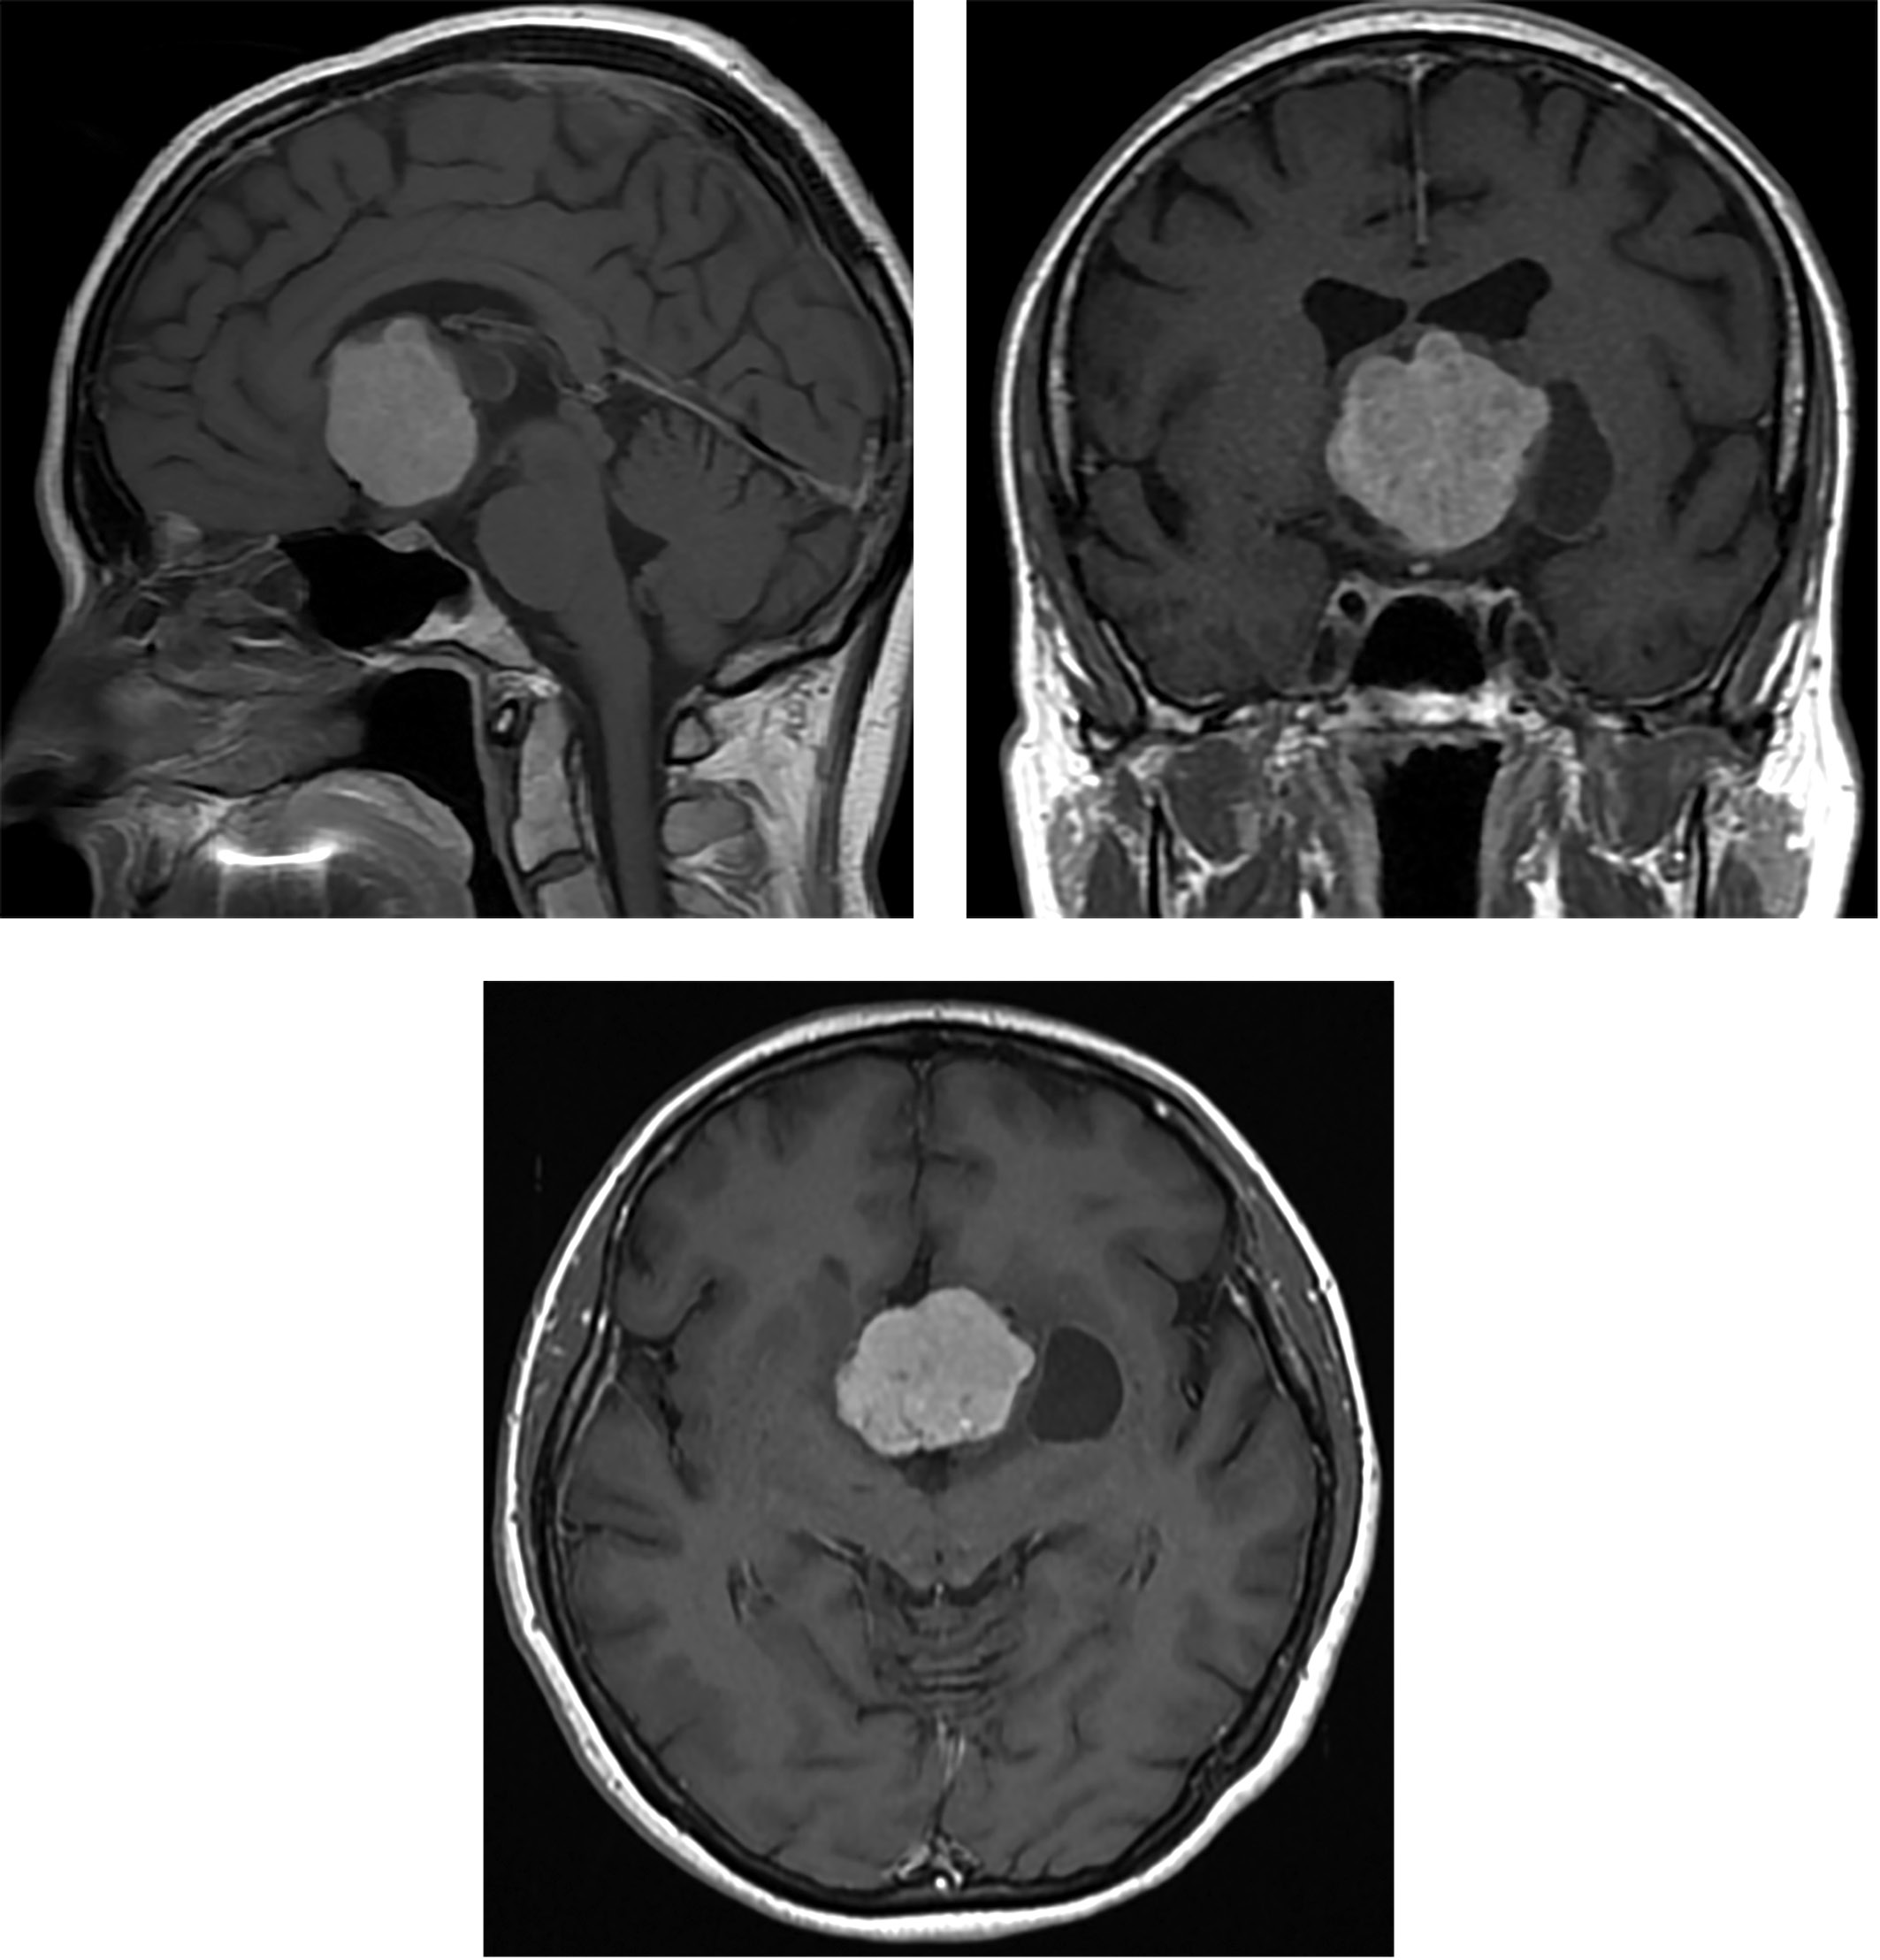

По данным магнитно-резонансной томографии головного мозга с внутривенным контрастированием в проекции III желудочка определялось крупных размеров образование с неоднородной структурой с наличием кист и перифокального отека, вызывающее компрессию и смещение хиазмы. После введения контраста отмечалось выраженное накопление контрастного вещества самим образованием и слабо выраженное в стенке кисты (рис. 1).

Рисунок 1. МРТ головного мозга с контрастированием пациентки З.

Визуализируется крупных размеров образование

в проекции третьего желудочка с неоднородной структурой,

наличием кист и перифокального отека,

вызывающее компрессию и смещение хиазмы.